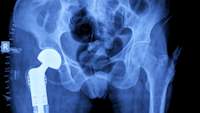

脆弱性骨折

如果你只是支离破碎的骨头容易骨质疏松症(臀部,脊柱、肱骨、肋骨、骨盆、和手腕),和有一些风险因素(说,你是绝经后妇女或有家族史的多孔骨),你的医生甚至没有检查你的骨密度,知道你的情况。单是骨折就足以确诊了。

骨密度扫描

不过,你的医生很可能会送你去做骨密度扫描,这是一种测量你的骨密度(BMD).最常见的BMD测试是a双能x线吸收仪或骨密度这被称为DXA或DEXA扫描。它使用低水平的辐射来测量即使是少量的骨质流失。它通常是在放射科或医疗办公室的门诊基础上在脊柱下部和臀部进行的,需要不到30分钟。穿舒适的没有拉链的衣服,让你的技术人员知道你是否有可能怀孕。你还需要在测试前24小时避免补充钙。

你的BMD结果以一个叫做a的数字分数的形式出现t指数这是一种衡量你的骨骼与30岁同性成年人的水平的指标。现在,如果你已经75岁了,这似乎不公平,对吧?那么,为什么是30岁?这是我们通常达到骨量峰值的时间,所以测试会显示从那时起你的骨量偏离了多远(或少)。如何阅读你的T-score?

- -1或更高被认为是正常的,你有健康的骨骼

- 考虑-1.1到-2.4骨量减少低骨密度不是骨质疏松症

- -2.5及以下是骨质疏松症——有骨折风险的柔软易碎的骨头

T-score可以帮助你的医生决定最好的骨质疏松治疗方法。